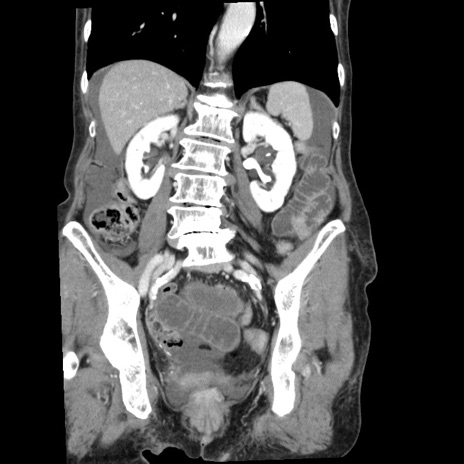

症例1(冠状断像)

【症例】80歳代女性

【主訴】腹痛

【現病歴】8時間前から腹痛あり来院。

【既往歴】糖尿病、脂質異常症、子宮体癌にて子宮全摘術

【身体所見】意識清明・会話良好だが腹痛で苦悶様、全腹部にわたって反跳痛と圧痛あり

【データ】WBC 13600、CRP 0.14、LDH 224、CK 90